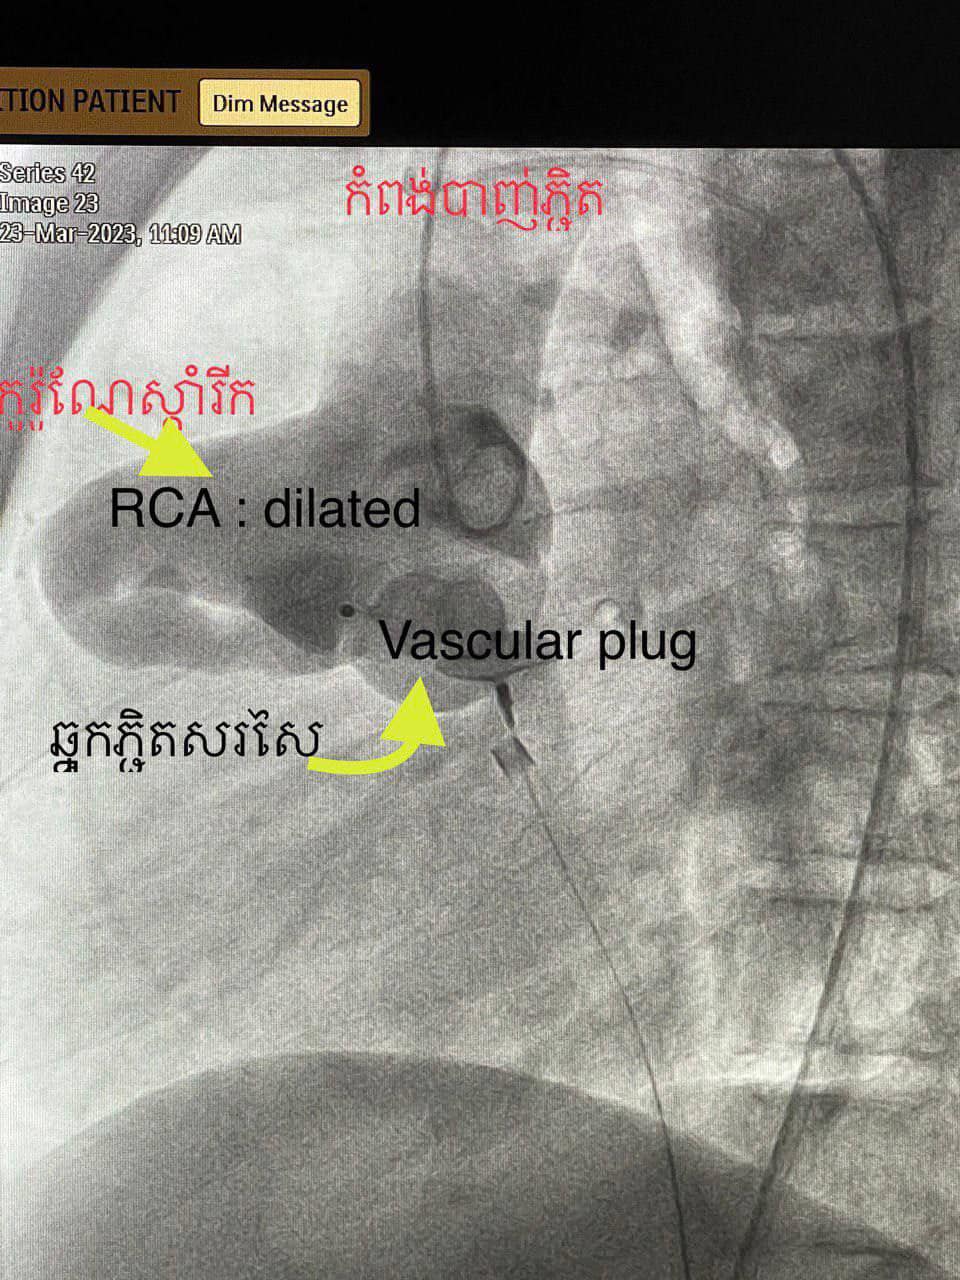

ខេត្តសៀមរាប៖ នៅថ្ងៃទី២៧ ខែមីនា ឆ្នាំ២០២៣ យោងតាមការចុះផ្សាយរបស់ មន្ទីរពេទ្យគន្ធបុប្ផា បានឱ្យដឹងថា ក្មេងប្រុស អាយុ១៣ឆ្នាំ មកពីស្រុកជើងព្រៃខេត្តកំពង់ចាម ដោយអាការៈចុកទ្រូងខ្លាំងរយៈពេល៥ថ្ងៃ ពេលមកដល់មន្ទីរពេទ្យជ័យវរ្ម័នទី៧ គ្រូពេទ្យឯកទេសផ្នែកបេះដូងបានធ្វើរោគវិនិច្ឆ័យយ៉ាងច្បាស់លាស់ថាជាការរីកសរសៃកូរ៉ូណែខាងស្តាំដោយចរន្តឈាមកូរ៉ូណែខាងស្តាំឆ្លងចូលថតបេះដូងស្តាំខាងលើ( RCA fistula to RA)។

ដូចនេះហើយក្រុមវេជ្ជបណ្ឌិតឯកទេសផ្នែកបេះដូងយើងបានរៀបចំដាក់កម្មវិធីបាញ់ភ្ជិតអោយក្មេងប្រុសម្នាក់នេះដោយបច្ចេកទេសទំនើបបំផុតមួយ catheterization to close RCA fistula to RA by vascular plug ប្រកបដោយភាពជោគជ័យ។